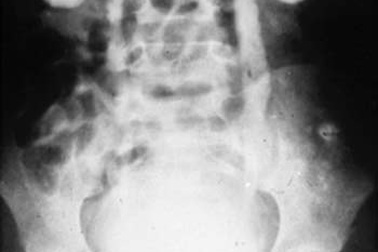

Bé trai 11 tuổi bị bệnh thận ứ nướcTheo thông tin từ Bệnh viện Nhi Đồng 2, TPHCM, bệnh viện này vừa thực hiện thành công ca phẫu thuật đầu tiên điều trị bệnh thận ứ nước ở trẻ em bằng phương pháp nội soi, bệnh nhân là Nguyễn văn K (ở Đồng Nai), 11 tuổi.

Phẫu thuật nội soi thành công hai trường hợp thận ứ nướcBệnh viện Nhi Đồng 2 vừa thực hiện thành công hai ca phẫu thuật nội soi cho trường hợp của hai bệnh nhi bị thận nước. Phương pháp phẫu thuật hiện đại này không gây ảnh hưởng đến các tạng trong ổ bụng, mất ít máu, bệnh nhi ít đau và hồi phục sớm.